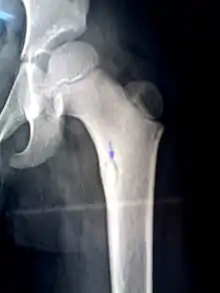

Sequestrum

A 'sequestrum' (plural: sequestra) is a piece of dead bone[1] that has become separated during the process of necrosis from normal or sound bone.

it is a complication (sequela) of osteomyelitis. The pathological process is as follows: